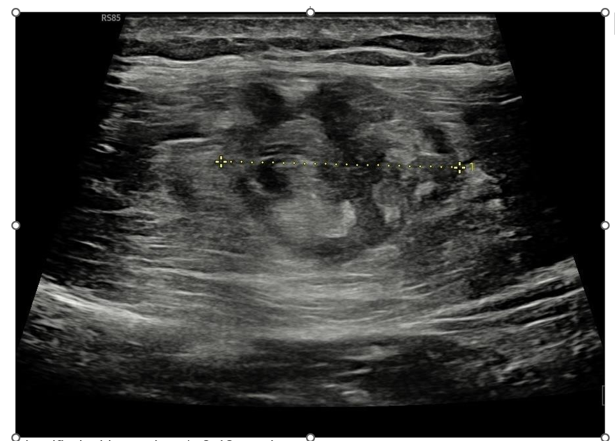

Ultrasound imaging revealed an intramuscular fluid collection and partial separation of the muscle fibers within the rectus femoris, consistent with an intramuscular degloving lesion (Figure 1&2).

Figure 1 Tranverse ultrasoud image of rectus femoris muscle

Measure identified with number 1: 2.42 centimeters.

Though less specific, ultrasound offers useful initial assessment: hypoechoic fluid collection, subtle fiber separation, and altered echotexture in the inner muscle portion may be visible, especially with high-frequency probes. In our case, ultrasound revealed the fluid plane and fascial separation, consistent with IDI. However, its sensitivity for quantifying retraction or distinguishing subtle separation is limited. Thus, MRI remains essential for comprehensive evaluation and prognostication.2,4